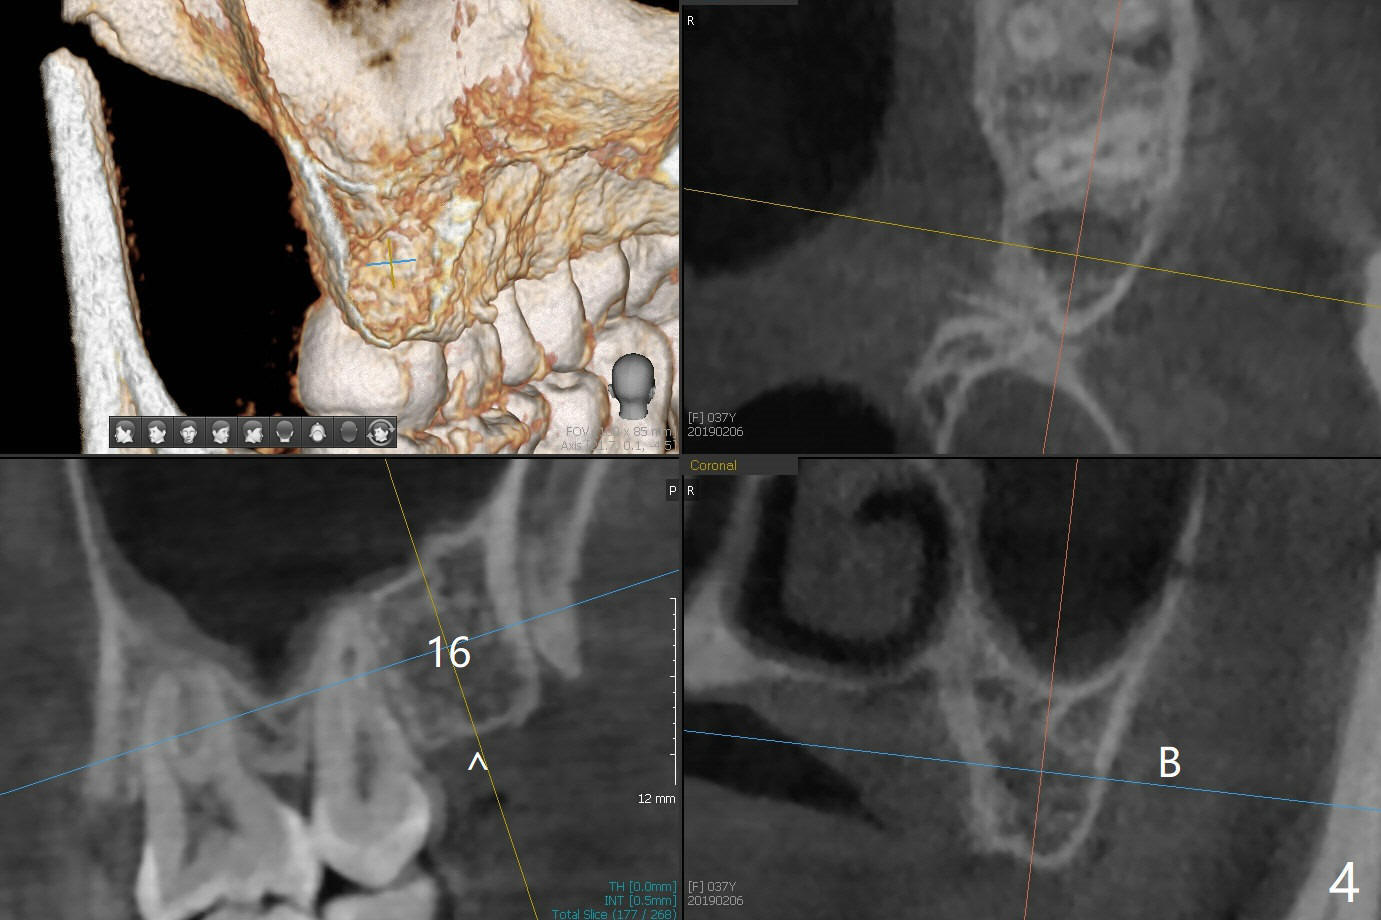

A 34-year-old lady requests extraction of #1, 16 and 32 (Fig.1). After incision for 32, surgical bur is used to create a purchase point to protect the thin bone between #31 and 32. The tooth is extracted with straight elevators and forceps. The socket is large single. Osteogen plug is placed with 4-0 plain gut suture (x4). There is cortical formation in the crest at #1, 16 and 32 three years postop (Fig.2-6 *, arrowheads). The advantage of Osteogen plug over Augma is easy placement with less risk of loss (by dissolving by saliva).